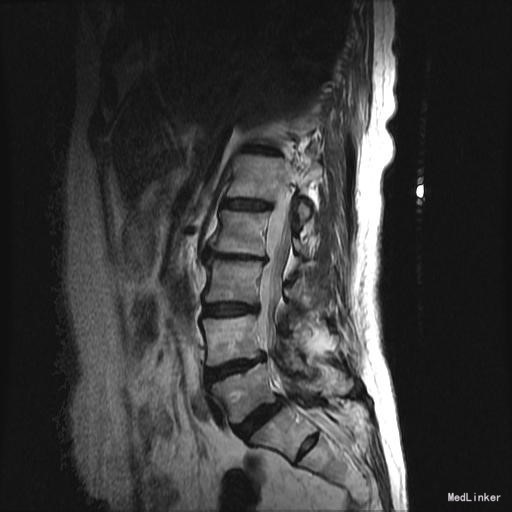

主诉:右下肢麻木11年,腰部酸痛无力 现病史:女性患者,65岁,患者于11年前无明显诱因下出现右下肢麻木,自大腿至右踝部,站立位加重。未予重视,后期出现腰臀部僵硬,弓背僵硬无力,自主行走距离不足200米,曾于06年经X线平片及MRI检查:腰椎椎管狭窄伴有腰椎滑脱,椎间盘突出等。

查体:侧弯畸形,右臀部及右下肢麻木疼痛,腰部活动受限,难以站立。右侧支腿抬高试验60°。双下肢肌力肌张力可。 辅助检查:平片:腰椎侧弯,椎体滑脱,曲度后凸 磁共振:L2-3,L4-5,L5-S1腰椎椎管狭窄,l2-3L3-4L4-5L5-S1腰椎间盘突出,腰椎退变

诊断: 腰椎侧弯,腰椎间盘突出 治疗:1期微创侧路椎体融合术+2期 微创后路经皮内固定术